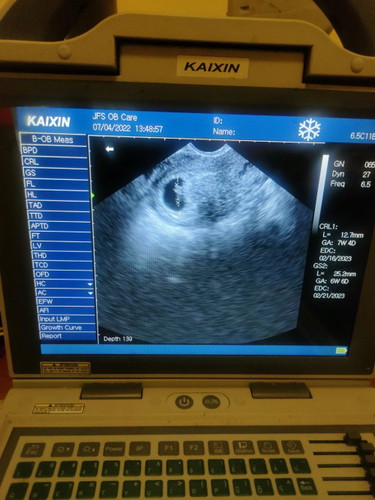

7 weeks and 4 days